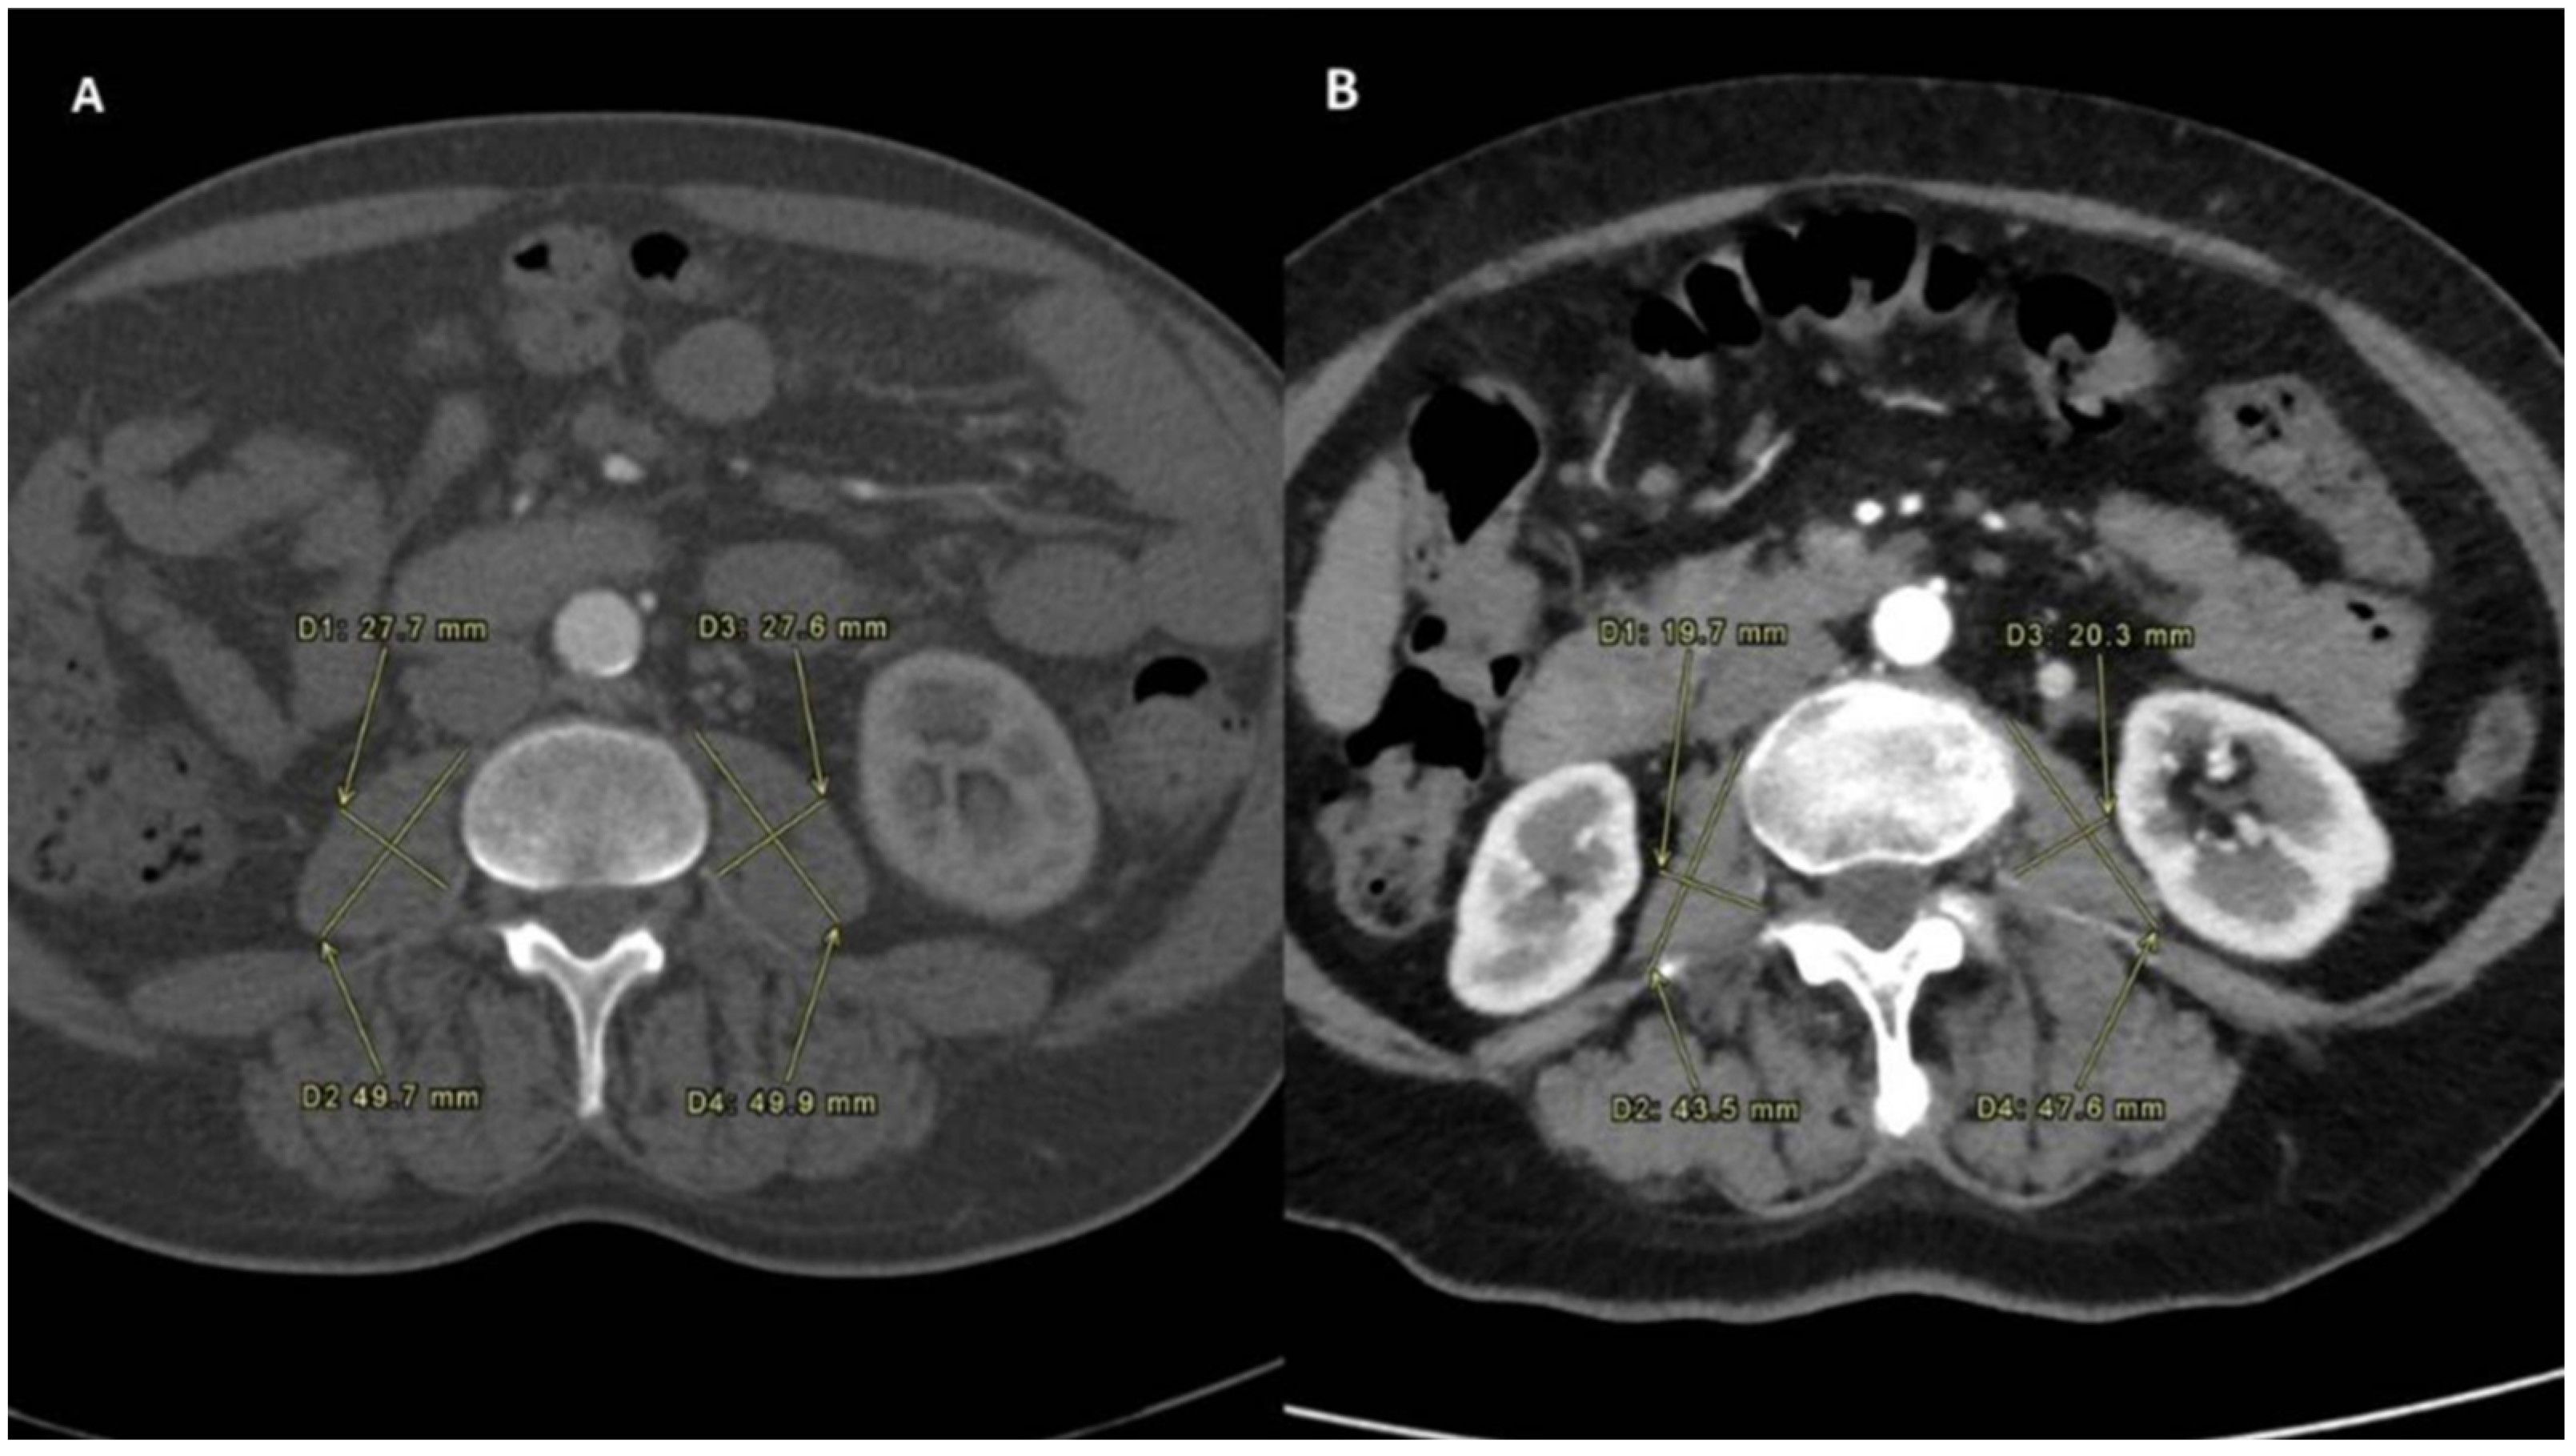

2.2. Sarcopenia Measurement